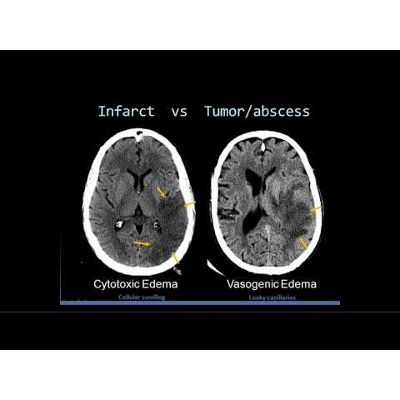

Intro to Head CT Part II: Evaluation of Ischemic Stroke (Presentation)